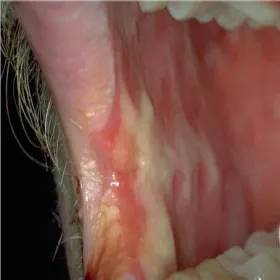

Jama ustna zespół Stevensa- Johnsona

Zespół Stevensa- Johnsona jamy ustnej